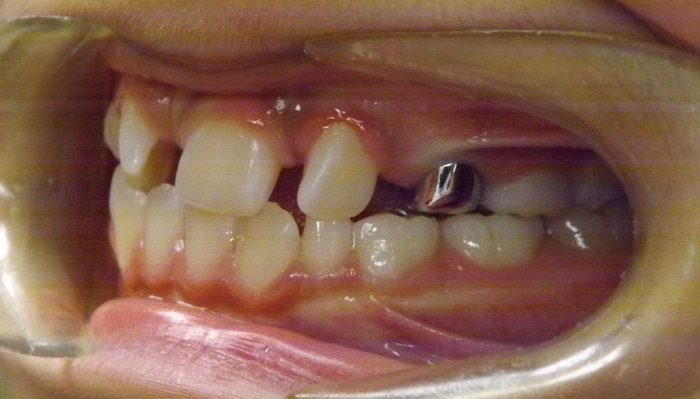

Christopher was a Phase I case that presented with a Class III bite on the right side and around a 90 degree rotation of his upper right central and lateral incisors. During Phase I we placed upper 2×4 brackets (brackets on upper 4 front permanent teeth) since he still had several primary teeth left. We began Phase II and at this time Christopher had 5 mm of upper crowding and 3 mm of lower crowding. We placed brackets on the upper and lower arches and had him wear elastics during treatment. Christopher ended with a really beautiful Class I bite and smile.